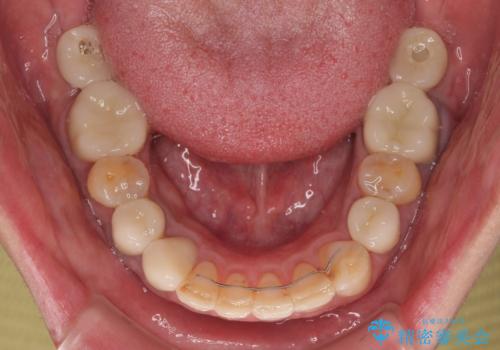

抜歯が必要な歯は事前に抜歯をし、その後ワイヤー装置にて歯列矯正を行い、途中でインプラントを埋入し、オールセラミッククラウンにて補綴治療を行うこととしました。

矯正治療にやや時間がかかりましたが、歯列はきれいに整い、気になっていたむし歯や銀歯は自然な色合いに仕上がりました。